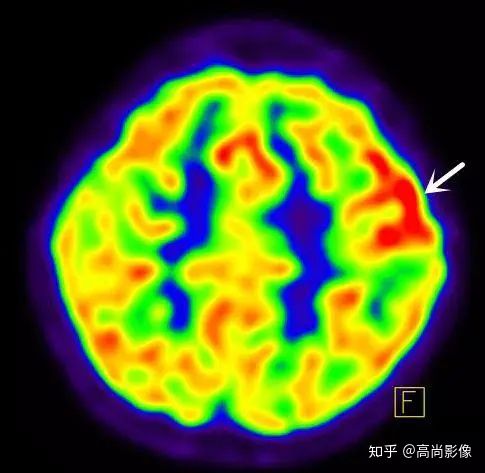

局部18F-FDG代謝顯像主要應(yīng)用于無創(chuàng)定位癲癇病灶。

在國際上,18F-FDG代謝顯像是無創(chuàng)定位癲癇病灶的標(biāo)準(zhǔn)。

發(fā)作間期癲癇灶呈代謝減低

發(fā)作期癲癇灶呈代謝增高